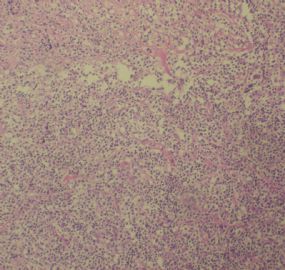

标本名称:  左前臂数个大小不等的皮下肿物。

既往有非何杰金淋巴瘤(滤泡性淋巴瘤)病史22个月。

• 左前臂数个大小不等的皮下肿物     淋巴瘤?图1

图1

病例不错。细胞胞浆透亮,间质血管丰富,图片不是很清晰,似乎有嗜酸粒细胞?

恶性,首先考虑T-NHL。IHC证实。

既往有NHL病史,图片不太清晰,细胞弥漫,胞浆透亮,首先考虑T细胞淋巴瘤。